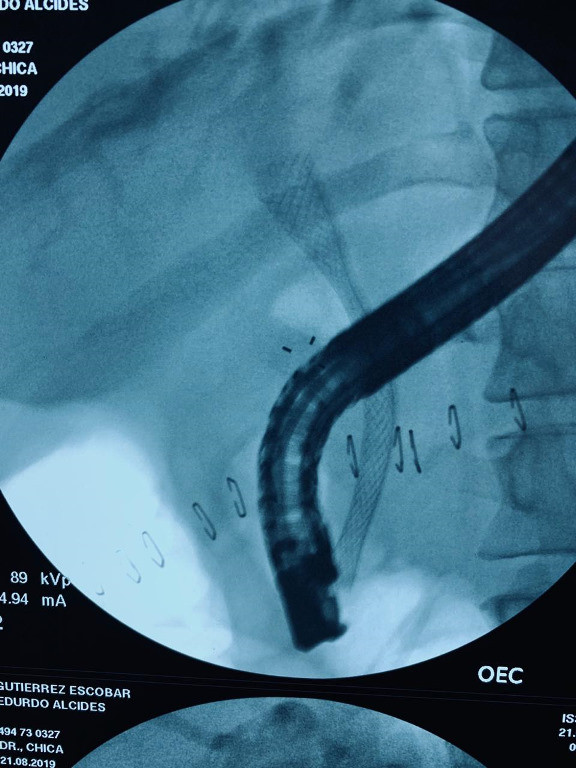

Paciente con cáncer de páncreas